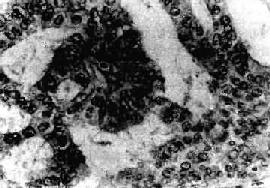

肉眼观,肌可以生长在子宫任何部位,常位于子宫壁内(肌层内肌)、浆膜下(浆膜下肌)或粘膜下(粘膜下肌)。可单发或多发,常为多个,其数目多少不等,常见为数个、乃至十数个或数十个,称多发性平滑肌。肌的大小可极为悬殊,小的在显微镜下才可检见,大的如成人拳大或更大,甚至可充满整个腹腔。肌多呈球形或融合成不规则形,质较硬,界限明显,但无明显包膜(图13-7)。切面上,组织常呈灰白色,编织状或旋涡状,当肌生长较快或供血不足时,可发生各种继发性改变,如玻璃样变、粘液变、囊性变、水肿出血、坏死等。

图13-7 子宫平滑肌

多个肌结节,位于肌壁内、粘膜下及浆膜下,境界分明,宫腔受挤压呈裂隙状